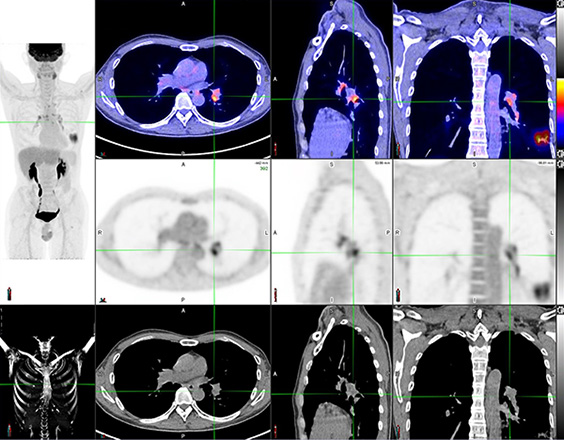

脑神经内分泌肿瘤

双示踪剂PET/CT (F-18 FDG及Ga-68 DOTATATE) 用於评估脑神经内分泌肿瘤体内的扩散情况

![]() [F-18] FDG |

![]() [Ga-68] DOTATATE |